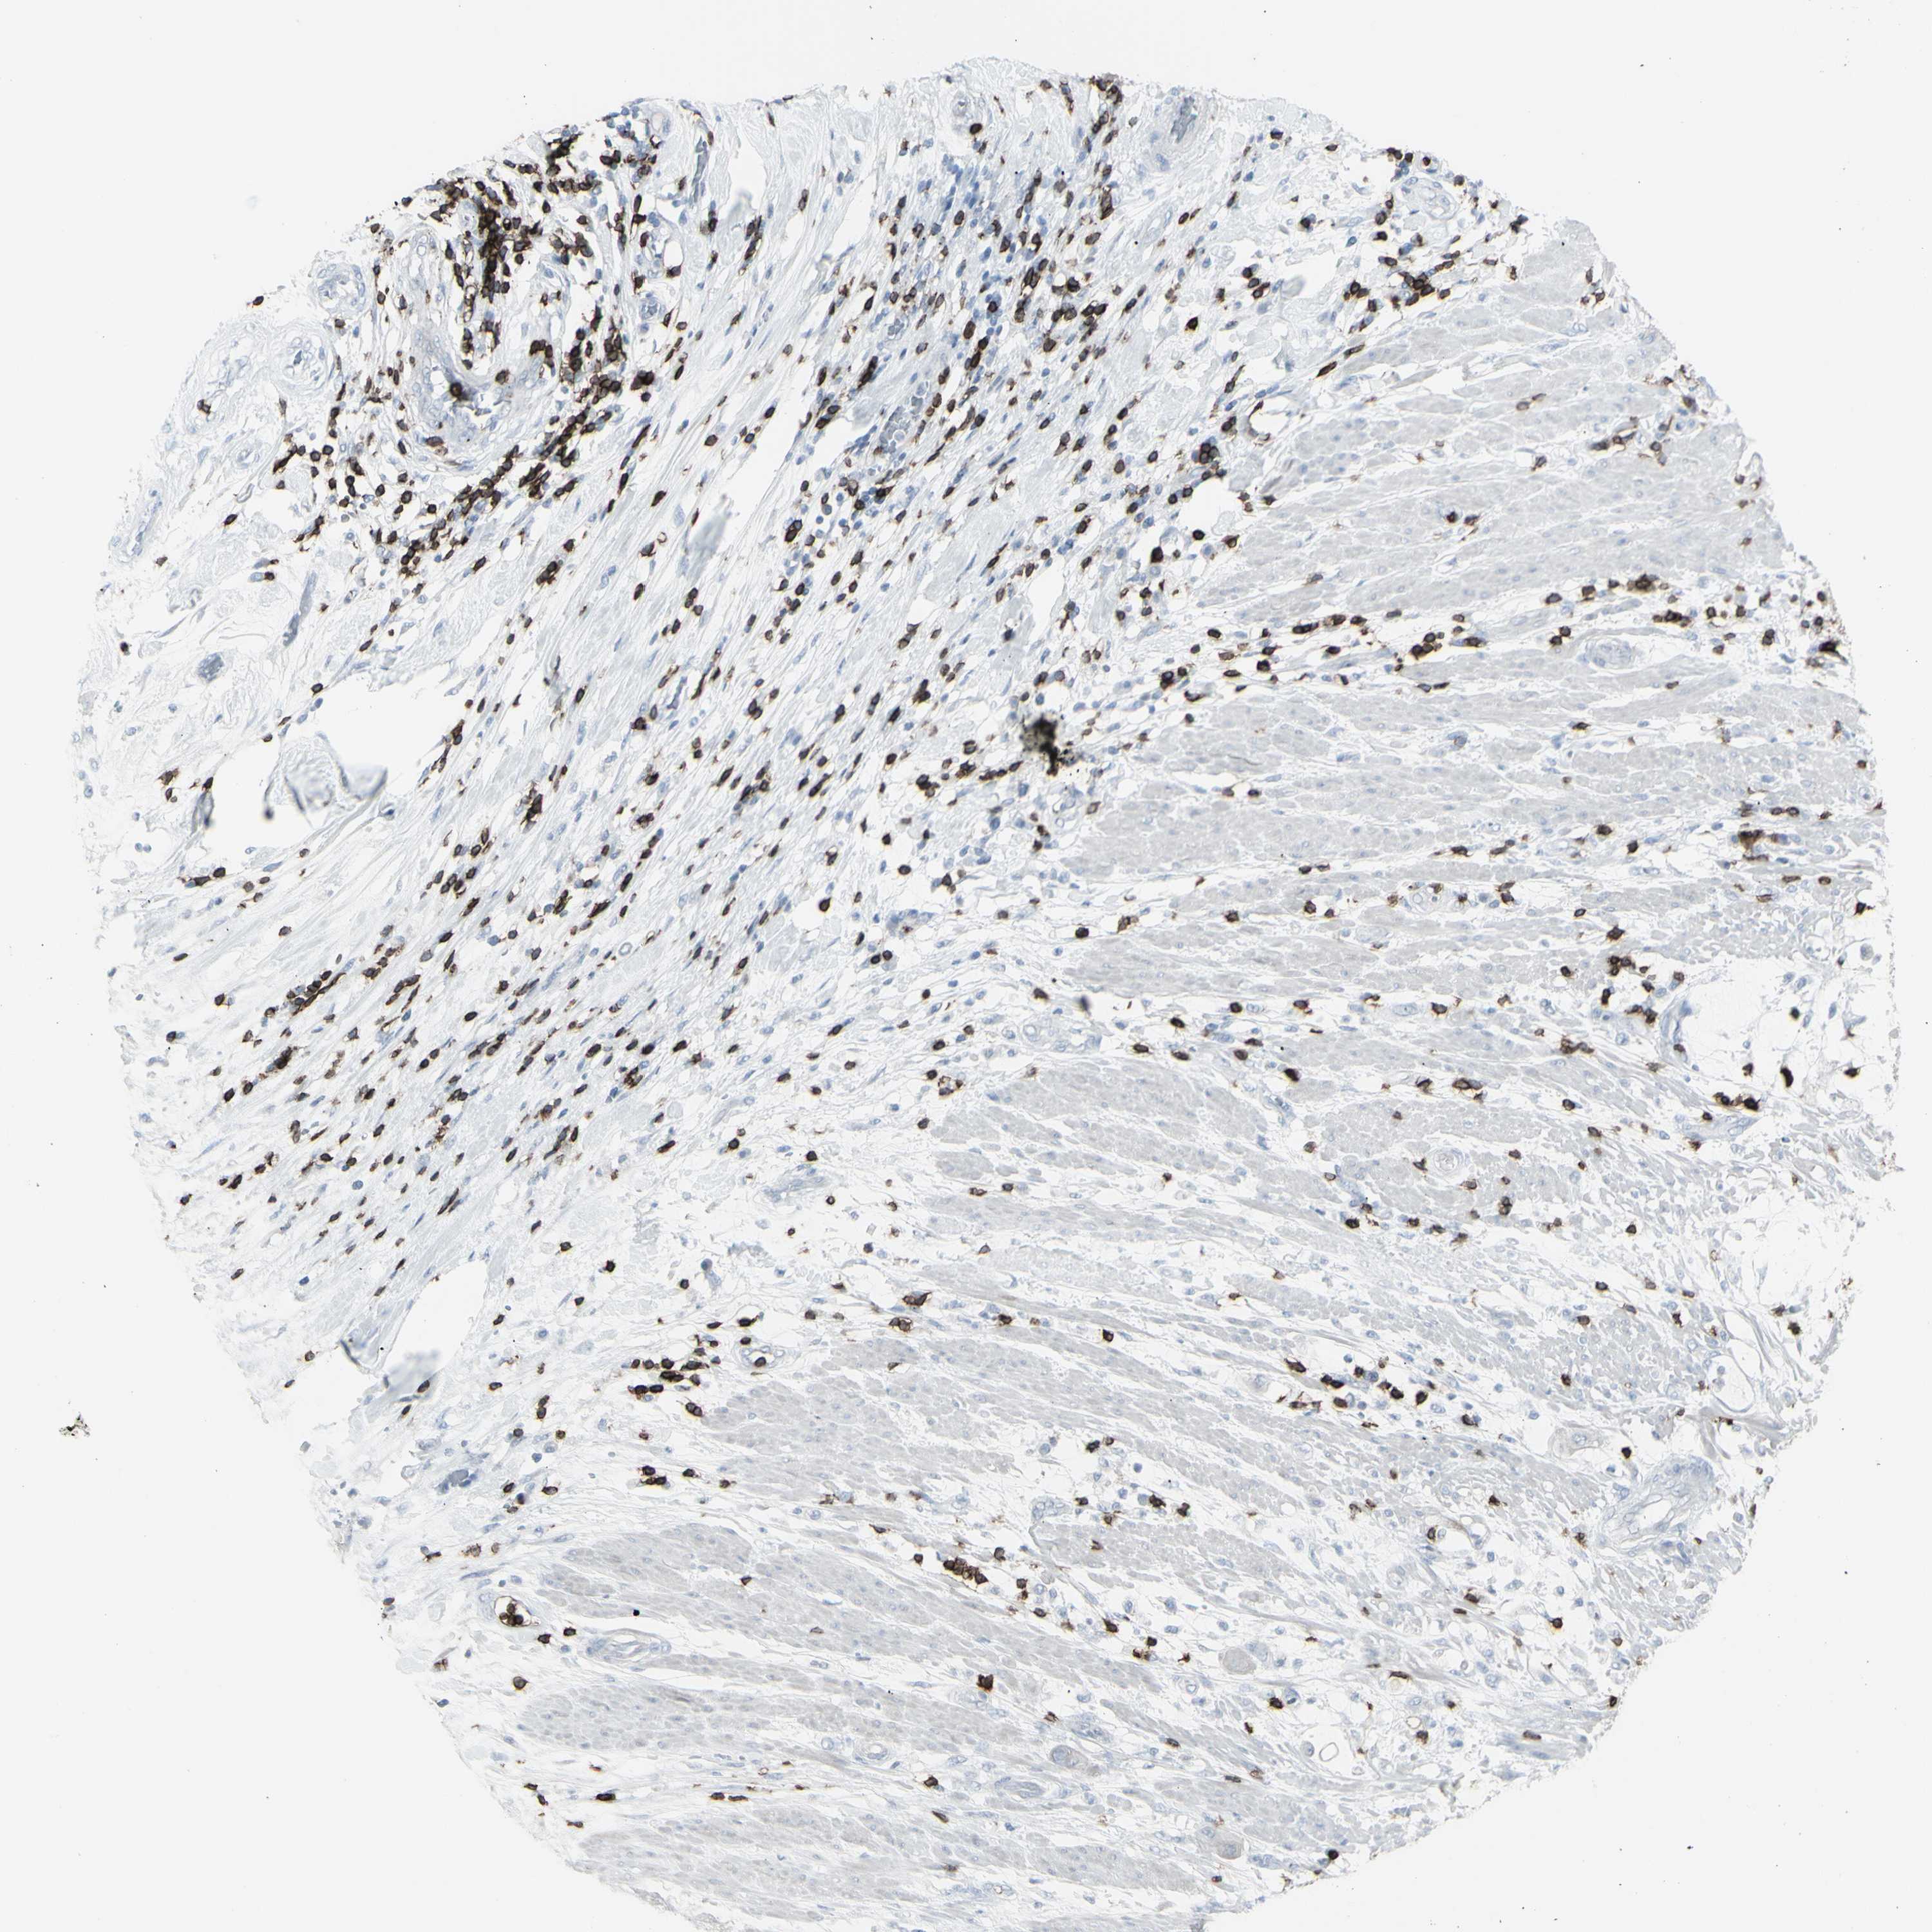

PANCREATIC CANCER - Protein expressioni

A mouse-over function shows sample information and annotation data. Click on an image to view it in a full screen mode. Samples can be filtered based on level of antibody staining by selecting one or several of the following categories: high, medium, low and not detected. The assay and annotation is described here.

Note that samples used for immunohistochemistry by the Human Protein Atlas do not correspond to samples in the TCGA dataset.

Antibody stainingi

Antibody staining in the annotated cell types in the current human tissue is reported as not detected, low, medium, or high, based on conventional immunohistochemistry profiling in selected tissues. This score is based on the combination of the staining intensity and fraction of stained cells.

Each image is clickable and will lead to virtual microscopy that enables deeper exploration of all samples and also displays staining intensity scores, fraction scores and subcellular localization as well as patient and tissue information for each sample.

Antibody HPA008750

Antibody CAB004651

Staining

High

Medium

Low

Not detected

Intensity

Strong

Moderate

Weak

Negative

Quantity

>75%

75%-25%

<25%

None

Location

Nuclear

Cytoplasmic/membranous

Cytoplasmic/membranous,nuclear

Adenocarcinoma, NOS

Adenocarcinoma, metastatic, NOS